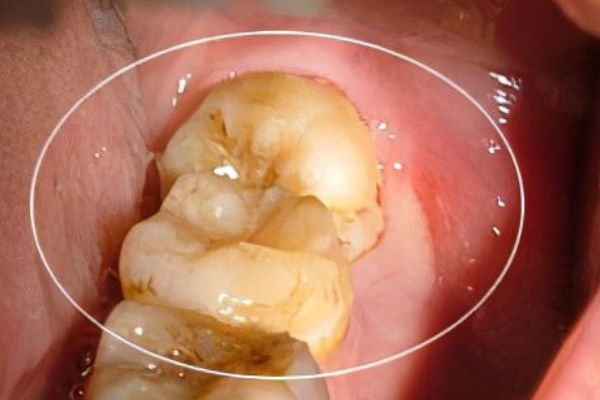

牙疼是一種令人難以忍受的痛苦,它讓人無法專注于任何事情,不僅影響個人的食欲和口腔健康,還會影響我們的情緒和生活質量。當牙齒發出刺痛的信號時,整個身體都會感受到它的存在。拔牙可以徹底解決牙疼問題,但拔后槽牙后悔死了,這是為什么呢?

后槽牙拔掉了,對人的咀嚼功能有非常大的影響,因為人的后槽牙是磨牙,是行使咀嚼功能的主要牙齒,一旦被拔掉,食物吃進嘴里無法得到精細的研磨,時間久了就容易引發胃腸消化系統的問題。所以對于磨牙來說,一定要盡力保留。

一些人牙疼去拔牙,但完全沒有意識到,后槽牙被拔了會影響到咀嚼功能,所以會出現拔后槽牙后悔死了的情況。盡管拔完之后,沒有了牙疼的困擾,但能夠保留和治療的話,還是不宜直接拔掉,即便實在沒有了治療價值,需要拔掉,也最好盡早鑲牙。